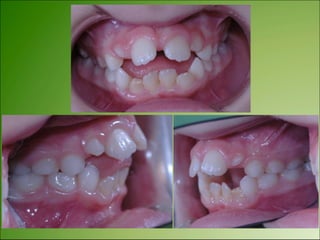

Disturbances of Dental Development

Most of them are contributors to isolate Class I malocclusion

with some other eruption problems. such as early loss of

primary teeth.

Dental problems related to larger congenital or health

problems include:

!

1. MISSING TEETH

1. Anodontia: failure of teeth to develop (same as agenesis

of teeth)

2. Hypodontia: having less than 6 congenitally missing

teeth.(partial anodontia)

3. Oligodontia: having 6 or more congenitally missing teeth

Upper lateral incisor

Lower central incisor

Hypodontia

UNILATERAL OR BILATERAL MISSING TEETH

The care of patients with congenitally missing lateral incisors is best

achieved through a multi-disciplinary approach.

It was acknowledged that a number of treatment options are

available to the patient, including canine substitution, tooth-

supported restorations and implant-supported restorations.

Each offers a number of advantages and disadvantages, and there

remains a relatively weak evidence base for these decisions

CONGENITALLY MISSING LATERAL INCISORS